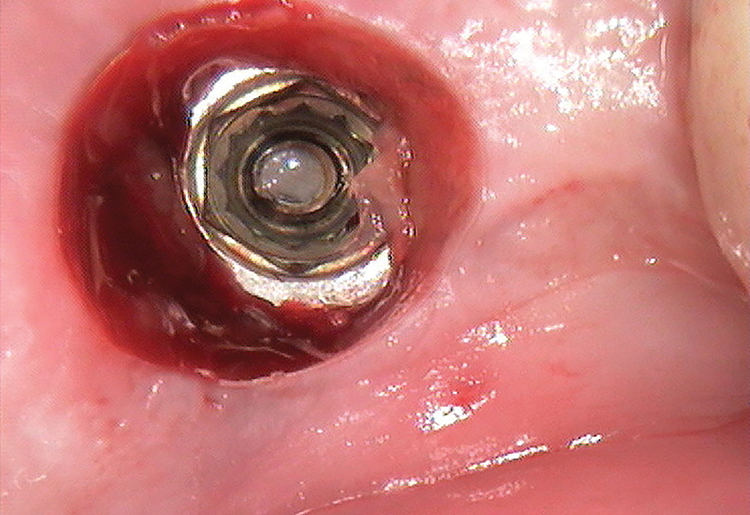

After the soak was complete, an ultrasonic tip was used with copious irrigation in a counterclockwise motion in short intervals to further loosen the screw fragment. The short intervals helped to reduce the amount of heat produced while still providing efficacy. After several rounds with the ultrasonic tip, a 25-gauge metal cannula was used to engage the top of the screw fragment and help rotate it in a counterclockwise direction. This use of the cannula was alternated with the ultrasonic tip to gain adequate movement of the fragment (Figure 6). Once the screw fragment was able to be retrieved, it was removed with the narrow suction tip (Figure 7). A healing abutment was then placed to contour the tissue until adequate healing occurred.